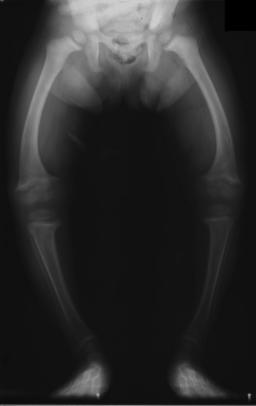

Researchers said that her remains reveal the woman had rickets in the breastbone, arms, ribs, and legs. Lead archaeologists went as far as saying this woman may have had one of the earliest cases of vitamin D deficiency ever found in the United Kingdom.

The bones had been excavated from the site in a northwestern village called Balevullin on the Scottish island, Tiree. Archaeologists believe that the woman had been around the age of 25 to 30 years old when she died. The skeleton showed that she was most likely four feet, nine inches tall.

Surprisingly, by Neolithic standards, she had been very short – the average Neolithic woman was about five feet, five inches.

She would have appeared to have a pigeon chest with misshapen limbs and a hunched position. This would explain why she was so crunched in her grave.